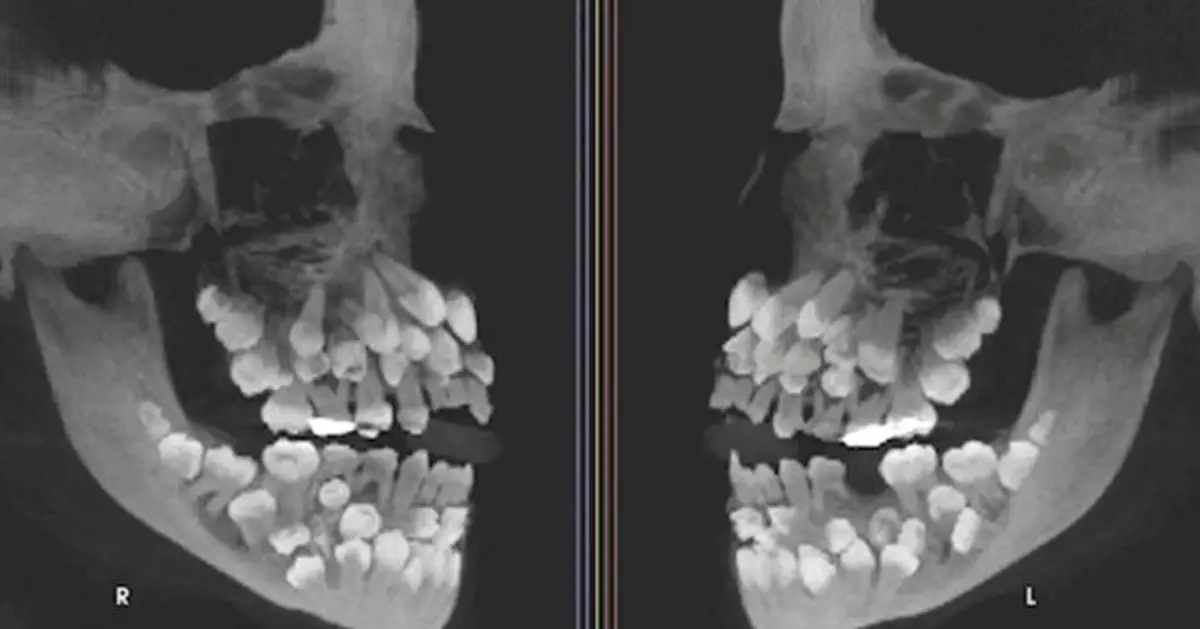

據外媒報導,這位來自巴西米納斯吉拉斯州(Minas Gerais)的女孩,原本想拔一顆上排的乳牙,但X光顯示她口中藏有18顆乳牙、32顆恆牙,以及31顆多生牙,總共高達81顆。

一般成人正常牙齒數為32顆

一般成人正常牙齒數為32顆,而超出正常數量的額外牙齒被稱為「多生牙」,通常多生牙數只有1至2顆,如此多多生牙的情況極為罕見。多生牙通常隱藏在牙齦內,可能干擾正常牙齒排列,甚至導致其他問題如囊腫等。